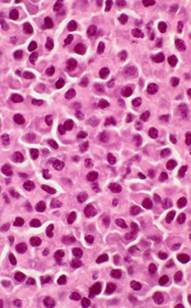

Figure 2: Microscopic view of biopsy tissue demonstrating abnormal plasma cells.